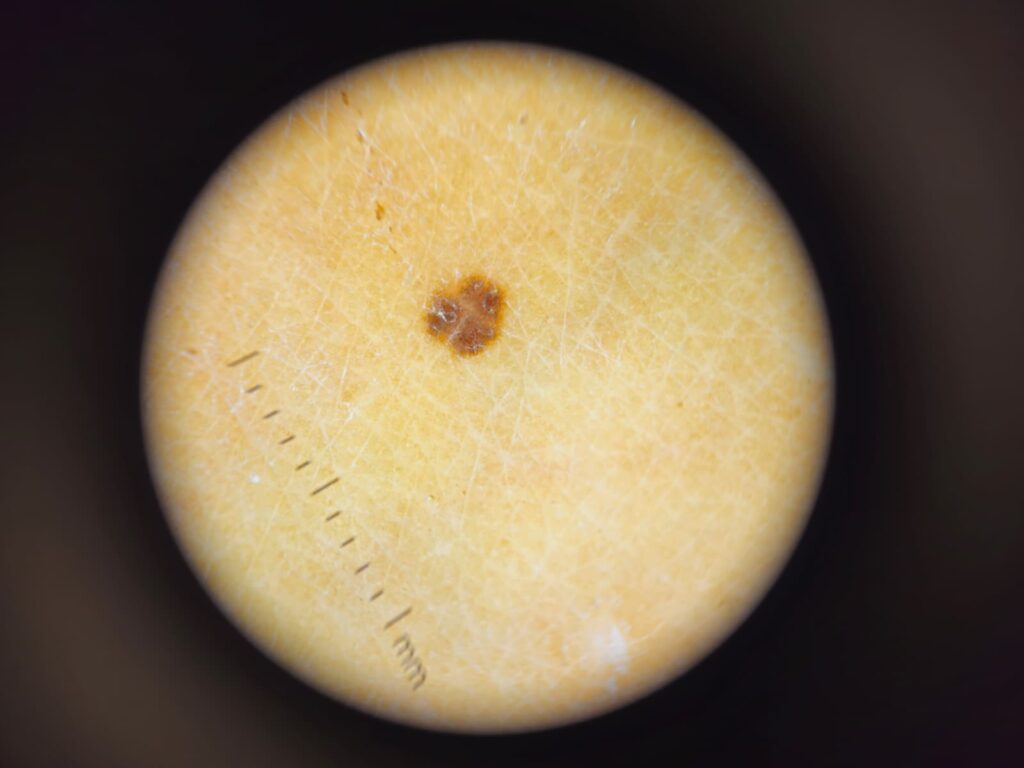

Dermatoskopia zmian skórnych

nieinwazyjne, bezbolesne badanie skóry, które pozwala na dokładną ocenę znamion barwnikowych („pieprzyków”) oraz innych zmian skórnych. Badanie wykonywane jest przy użyciu dermatoskopu – specjalnego urządzenia powiększającego, umożliwiającego lekarzowi obejrzenie struktur skóry niewidocznych gołym okiem.

Badanie polega na przyłożeniu dermatoskopu do powierzchni skóry. W trakcie wizyty oceniana jest skóra całego ciała, ze szczególnym uwzględnieniem znamion barwnikowych oraz zmian budzących wątpliwości. Lekarz analizuje strukturę zmiany, jej symetrię, barwę oraz inne cechy charakterystyczne.